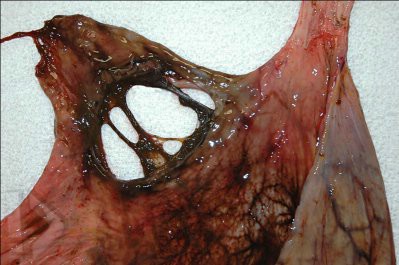

Imagens Para Você Ver Antes De Jantar- II